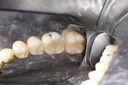

Wes Sato #14 pre-op